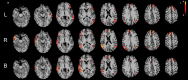

Purpose To measure the accuracy of resting-state functional magnetic resonance (MR) imaging in determining hemispheric language dominance in patients with medically intractable focal epilepsies against the results of an intracarotid amobarbital procedure (IAP). Materials and Methods This study was approved by the institutional review board, and all subjects gave signed informed consent. Data in 23 patients with medically intractable focal epilepsy were retrospectively analyzed. All 23 patients were candidates for epilepsy surgery and underwent both IAP and resting-state functional MR imaging as part of presurgical evaluation. Language dominance was determined from functional MR imaging data by calculating a laterality index (LI) after using independent component analysis. The accuracy of this method was assessed against that of IAP by using a variety of thresholds. Sensitivity and specificity were calculated by using leave-one-out cross validation. Spatial maps of language components were qualitatively compared among each hemispheric language dominance group. Results Measurement of hemispheric language dominance with resting-state functional MR imaging was highly concordant with IAP results, with up to 96% (22 of 23) accuracy, 96% (22 of 23) sensitivity, and 96% (22 of 23) specificity. Composite language component maps in patients with typical language laterality consistently included classic language areas such as the inferior frontal gyrus, the posterior superior temporal gyrus, and the inferior parietal lobule, while those of patients with atypical language laterality also included non-classical language areas such as the superior and middle frontal gyri, the insula, and the occipital cortex. Conclusion Resting-state functional MR imaging can be used to measure language laterality in patients with medically intractable focal epilepsy. (©) RSNA, 2016 Online supplemental material is available for this article.